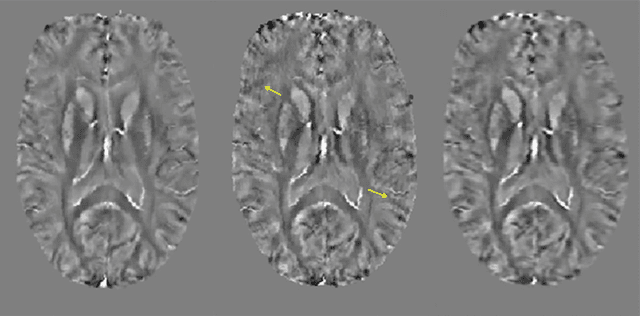

Abstract:Purpose: To develop a pipeline for motion artifact correction in mGRE and quantitative susceptibility mapping (QSM). Methods: Deep learning is integrated with autofocus to improve motion artifact suppression, which is applied QSM of patients with Parkinson's disease (PD). The estimation of affine motion parameters in the autofocus method depends on signal-to-noise ratio and lacks accuracy when data sampling occurs outside the k-space center. A deep learning strategy is employed to remove the residual motion artifacts in autofocus. Results: Results obtained in simulated brain data (n =15) with reference truth show that the proposed autofocus deep learning method significantly improves the image quality of mGRE and QSM (p = 0.001 for SSIM, p < 0.0001 for PSNR and RMSE). Results from 10 PD patients with real motion artifacts in QSM have also been corrected using the proposed method and sent to an experienced radiologist for image quality evaluation, and the average image quality score has increased (p=0.0039). Conclusions: The proposed method enables substantial suppression of motion artifacts in mGRE and QSM.